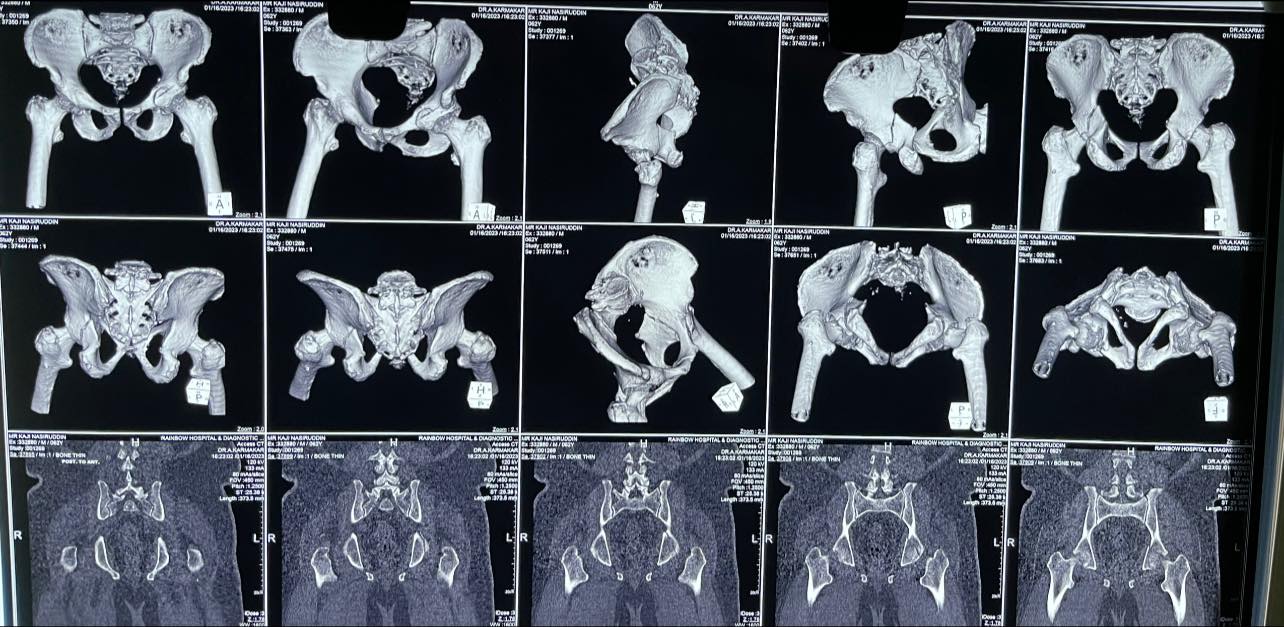

65 yr old male with acetabular fracture in the posterior column with anterior wall.

Such fractures used to be treated by just traction for months in the past. Now a days we follow the AO principle of absolute reduction and early mobilisation to give a better outcome to the joint.